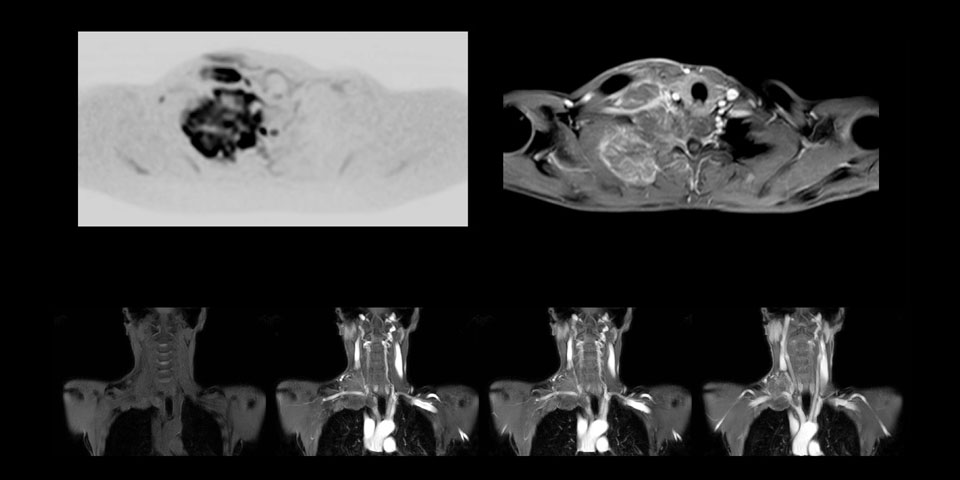

MR neurography of nerve sheath lesion

This patient is a 43-year-old female with a left supraclavicular nerve sheath tumor. The lesion is well visualized on the STIR VISTA images and on the MR neurography using DWIBS. The exam was performed on Prodiva 1.5T.

Whole body diffusion

MR neurography using DWIBS inverted, full MIP

Acq voxel size 1.2 x 1.3 x 2.4 mm, Recon voxel size 0.7 x 0.7 x 1.2 mm, dS SENSE factor 2, scan time 5:46 min.